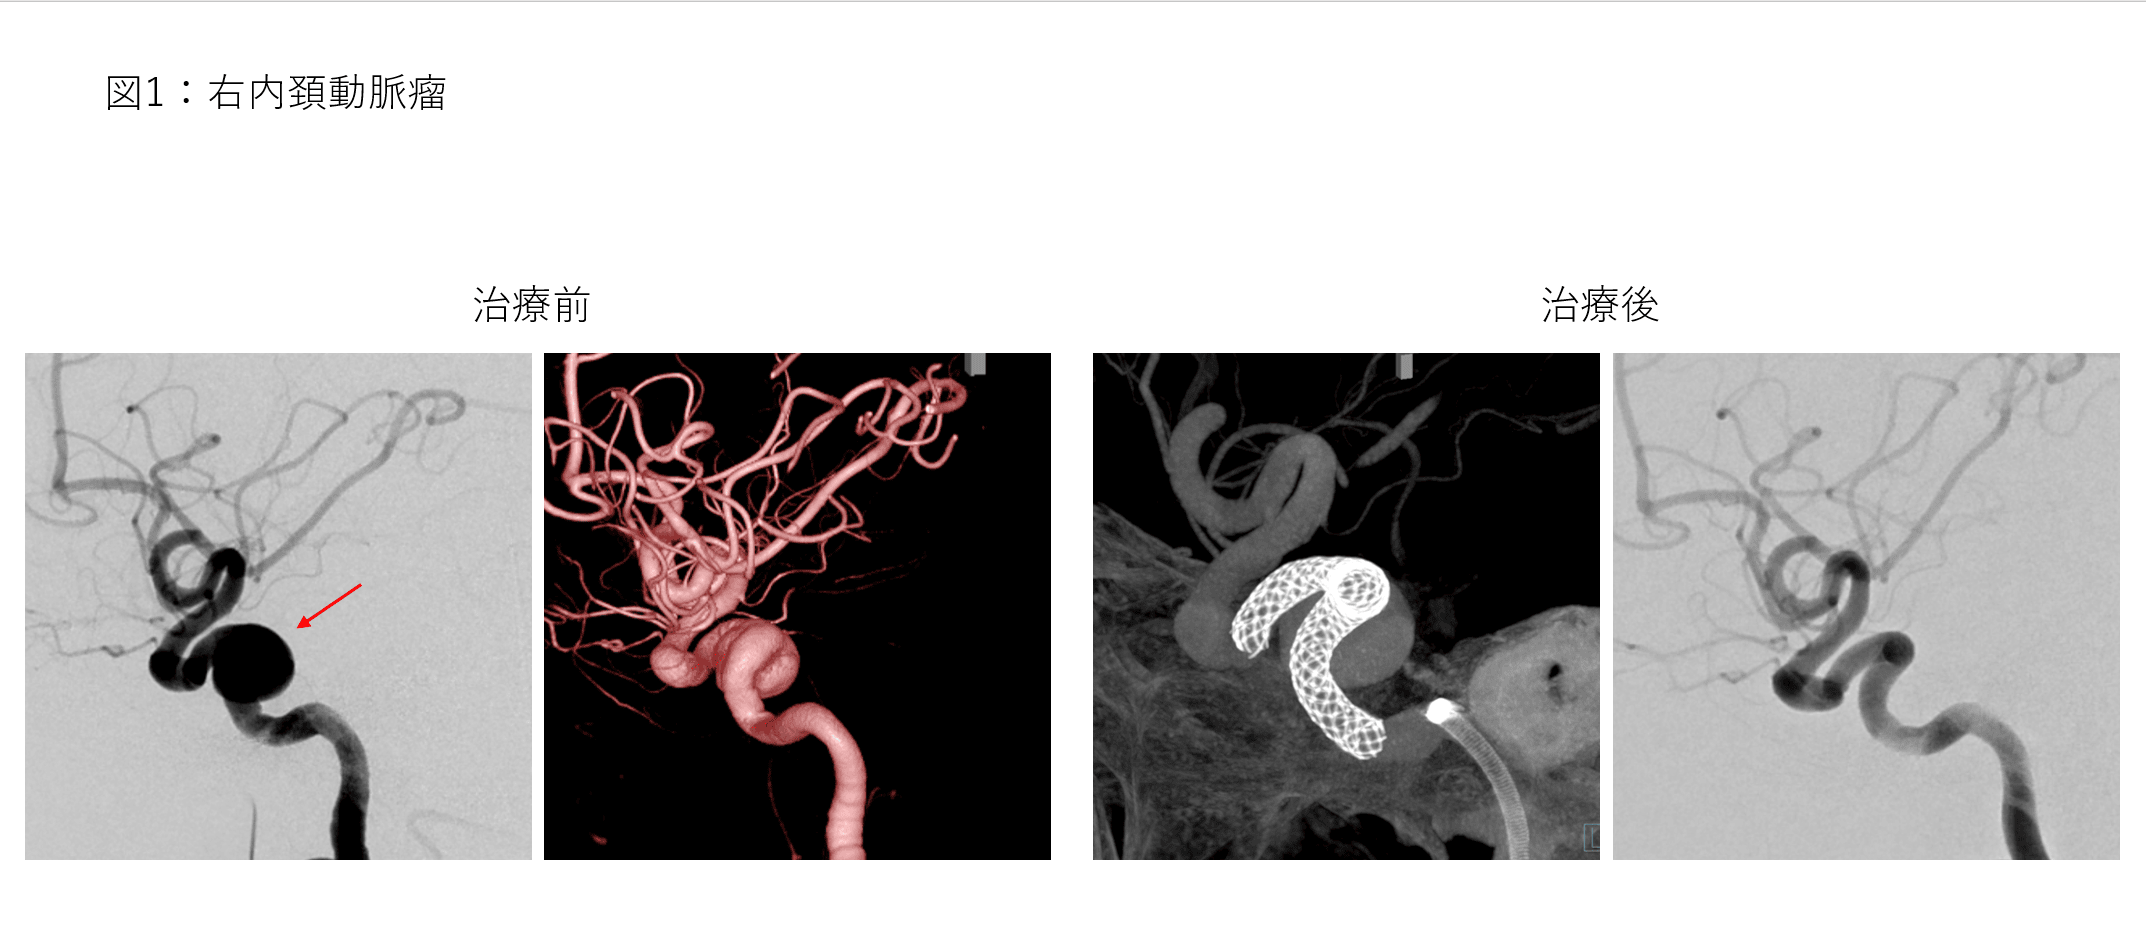

脳動脈瘤は部位、大きさ、形状などで治療の難しさが異なります。脳神経血管内治療では、塞栓用コイル(動脈瘤内を塞栓する器具)、ステント(筒状の形状をした編み込み形状の器具)を使用して、動脈瘤内部に血流が入らないように治療します(動脈瘤塞栓術)。

しかし通常行う動脈瘤塞栓術や外科手術(開頭クリッピング術など)での治療が難しい場合があります。

特に大型の内頚動脈瘤で部位的に外科手術での到達が難しい場合は、脳神経血管内治療が選択されますが、動脈瘤塞栓術で根治することが難しい場合が多いです。この場合は、内頚動脈内腔にフローダイバーター(網目の細かいステント、脳動脈瘤への血液の流れ込みを減らす効果がある)を留置します(図1)。脳動脈瘤内腔の血流が減り、経過とともに血栓化すると脳動脈瘤が閉塞し治癒に至ります。